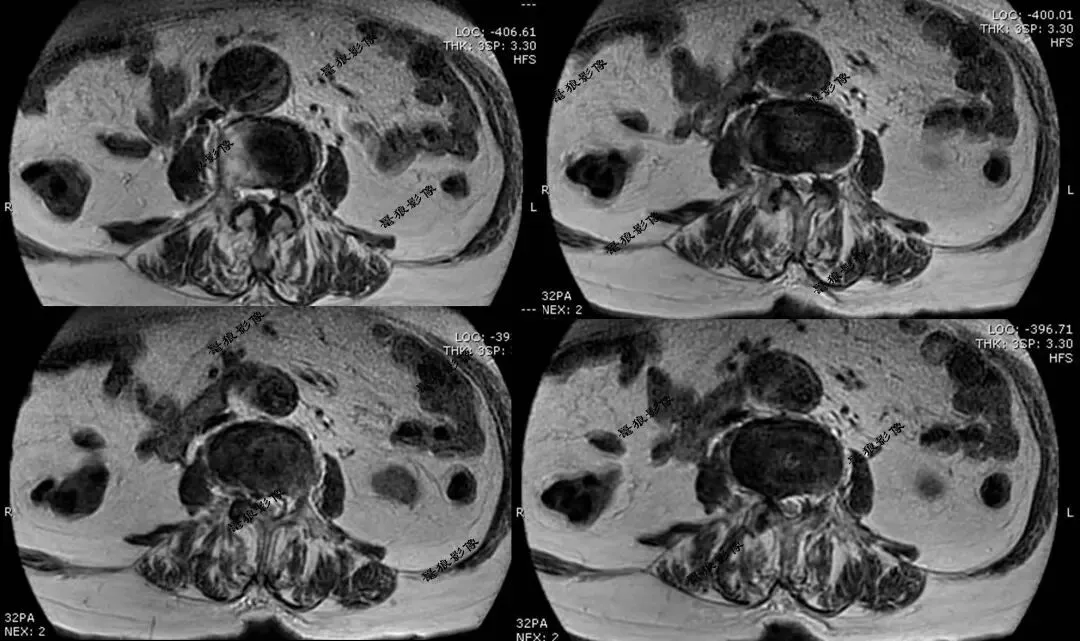

二、腰椎MR(术前)

考虑腹主动脉下段动脉瘤并附壁血栓。